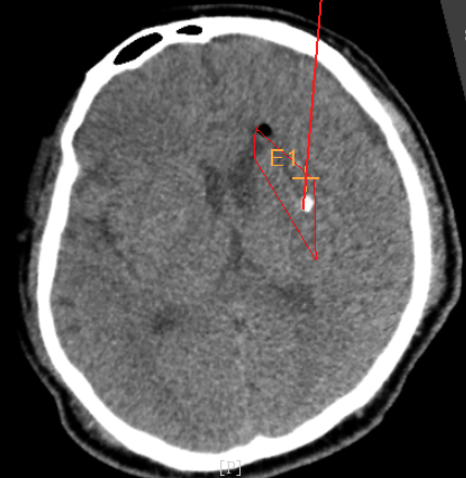

韓帥醫(yī)生借助機(jī)器人操作平臺(tái)順利抽出血性液體15ml,與術(shù)前軟件計(jì)算的血腫量完全一致,手術(shù)在30分鐘內(nèi)順利完成。

術(shù)中韓帥醫(yī)生借助“睿米”完成血腫抽吸

手術(shù)抽出血腫15ml

術(shù)后CT:血腫腔消失